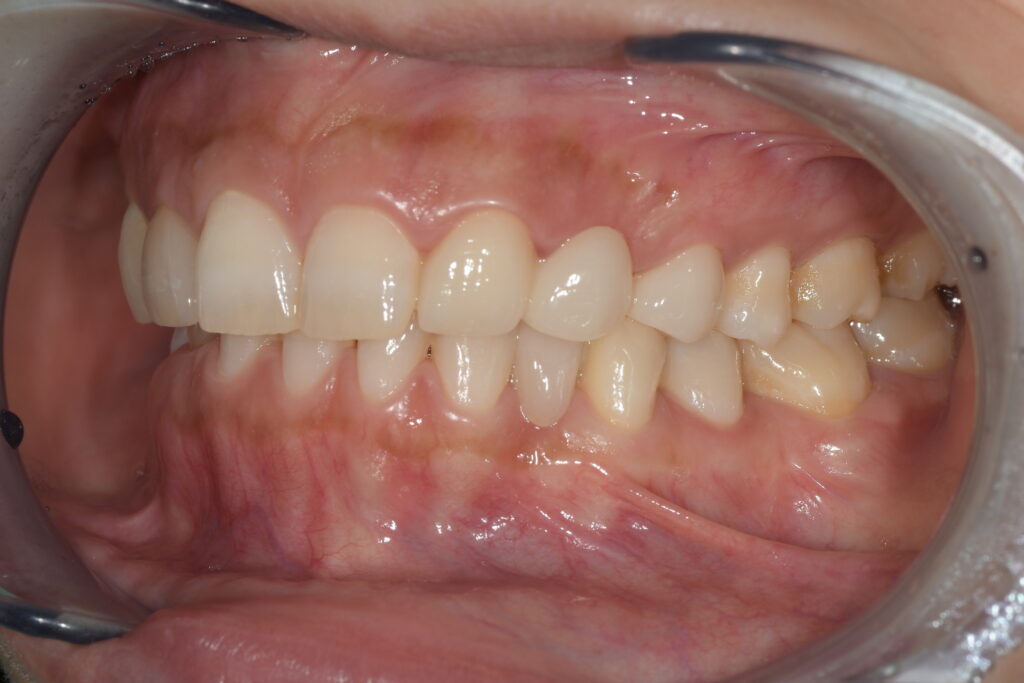

実際の当院での事例ですが

この方も乳歯が残っていたのが抜けてしまい、当時県外で保険診療で接着ブリッジを入れたそうです。

上下の歯をやりかえていきましたが、上の歯は虫歯や奥の削られていた歯の形の問題で通常のブリッジをセラミックで修復、下の歯は接着ブリッジでやりかえました。